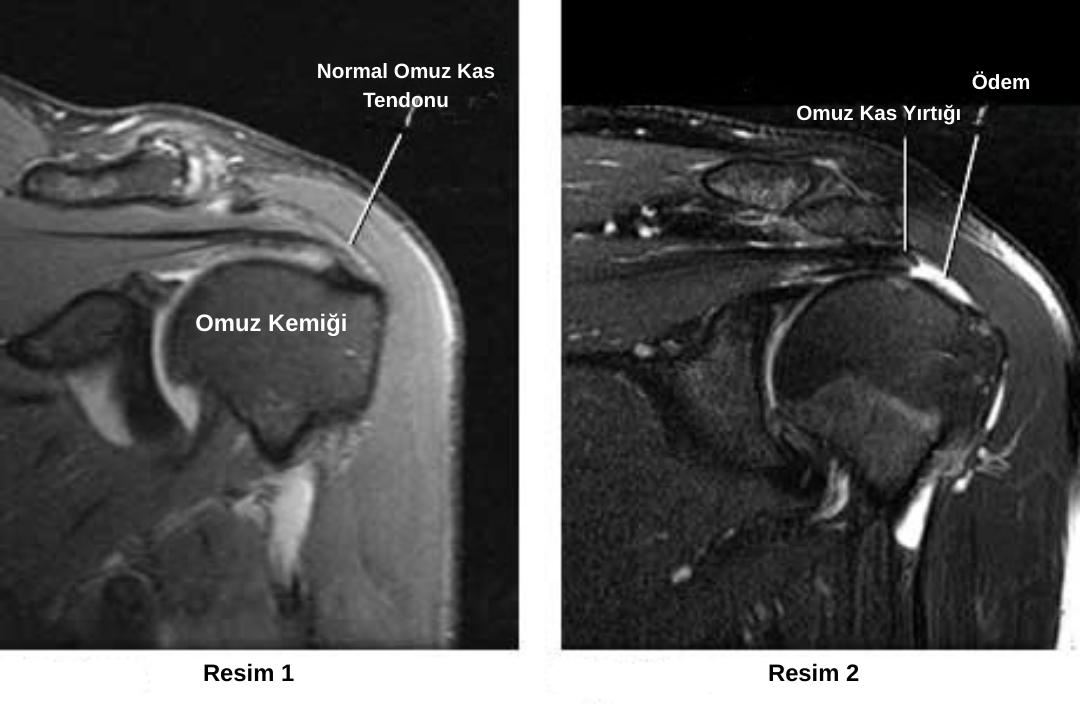

Tanıyı kesinleştirmek, yırtığın tam yerini, boyutunu ve kas dokusundaki olası yağlanmayı saptamak için en güvenilir yöntem Manyetik Rezonans Görüntülemedir (MR).